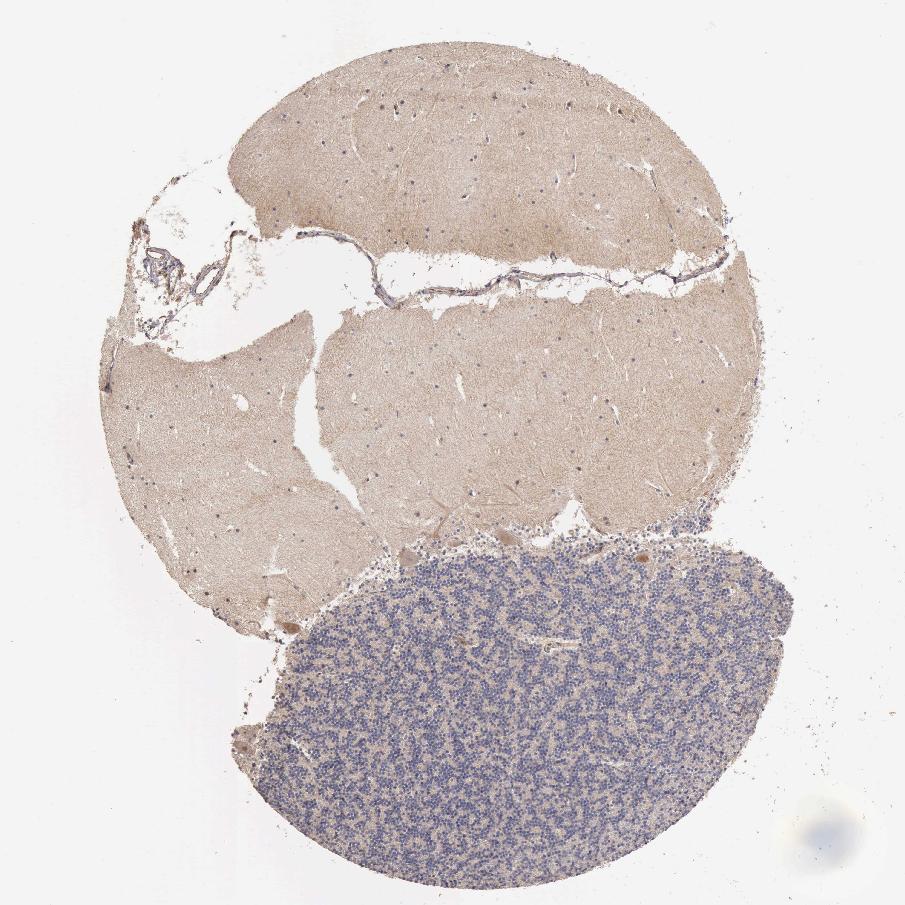

CEREBELLUM - Antibody stainingi

Antibody staining in the annotated cell types in the current human tissue is reported as not detected, low, medium, or high, based on conventional immunohistochemistry profiling in selected tissues. This score is based on the combination of the staining intensity and fraction of stained cells.

Each image is clickable and will lead to virtual microscopy that enables deeper exploration of all samples and also displays staining intensity scores, fraction scores and subcellular localization as well as patient and tissue information for each sample.

Antibody HPA001048Antibody CAB032495

Purkinje cells LowNot detected

Cells in granular layer Not detectedNot detected

Cells in molecular layer Not detectedNot detected